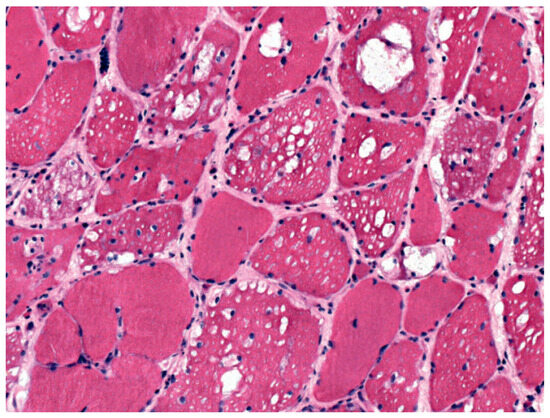

Die Glykogenose Typ II (Morbus Pompe)

by Thomas Hundsberger, Ursula Hohl, Barbara Erdèlyi and Kai M. Rösler

Swiss Arch. Neurol. Psychiatry Psychother. 2010, 161(2), 55-59; https://doi.org/10.4414/sanp.2010.02143 - 1 Jan 2010

Cited by 2 | Viewed by 43

Hundsberger T, Hohl U, Erdèlyi B, Rösler M. Glycogen storage disease type II (Pompe’s disease). Schweiz Arch Neurol Psychiatr. 2010;161(2):55–9. Glycogen storage disease type II (Pompe disease) is a rare autosomal recessive disorder due to mutations in the acid alpha-glucosidase (GAA) gene. [...] Read more.

Hundsberger T, Hohl U, Erdèlyi B, Rösler M. Glycogen storage disease type II (Pompe’s disease). Schweiz Arch Neurol Psychiatr. 2010;161(2):55–9. Glycogen storage disease type II (Pompe disease) is a rare autosomal recessive disorder due to mutations in the acid alpha-glucosidase (GAA) gene. The disease defining genetic alteration can be found at several nucleotides as more than 200 different mutations has been reported so far. Some of these mutations lead to a complete loss of function of the GAA whereas others only reduce enzyme activity to various degrees. Deficient GAA activity leads to harmful lysosomal glycogen storage and disruption of various cell types. Depending on the degree of residual enzyme activity symptoms of the disease evolve in infancy, childhood or adulthood. As a rule loss of enzyme function or low residual activity is associated with a severe phenotype and early onset disease. Glycogenosis type II is a multisystem disorder with a broad clinical spectrum. Muscle weakness and respiratory failure are the most important clinical symptoms in adults. In infants symptoms due to cardiomyopathy, arrhythmia and heart failure are most prominent and life threatening. Glycogen accumulation has also been detected in the brain, brainstem and anterior horn cells. Soon after birth first symptoms occur with a fast disease progression leading to death after 6–12 months in untreated patients (“classic form”). Infants with signs of generalized myopathy (floppy infant) and cardiomyopathy should be screened for Pompe’s disease as early enzyme replacement therapy (ERT) with recombinant human GAA (rhGAA) can prevent a lethal outcome. If the enzyme activity is more than 1% of the normal GAA activity children and adults have a more benign phenotype consisting of muscle weakness and ventilatory problems. In children developmental motor milestones are usually delayed or not reached (i.e., walking). Adults are affected by proximal myopathy and diaphragmal insufficiency (“late-onset form”). Diagnosis is based on the clinical suspicion of a proximal myopathy, a muscle biopsy showing intracellular glycogen accumulation and the biochemical measurement of GAA activity in lymphocytes, dried blood spots assays, skin fibroblast or muscle. The diagnosis should be confirmed by genetic testing at least for the most common IVS1 splice site mutation. ERT with rhGAA (Myozyme®) for this disease is worldwide available since 2006. For infants and children this therapy is well established despite high costs and the need for frequent intravenous infusions every other week in a dosage of 20 mg/kg body weight. Reconstitution of cardiomyopathy clearly improves survival and enhances quality of life compared with untreated children with a life expectancy of less than one year. The timing, duration and benefit of ERT in adults is still an open question. Due to the few published studies, reflecting the rarity of the disease, muscle strength and ventilator function improves under ERT. Early therapy seems to prevent disease progression. Unfortunately, there is no predictive marker for the beneficial effect of ERT therapy in Pompe patients. Nevertheless, a randomized, placebo-controlled trial of 90 “late-onset” patients ERT significantly improved walking and pulmonary outcomes. Keeping the high costs of therapy in mind and knowing the wide spectrum of clinical presentation the indication for ERT in “late-onset” patients must be considered on an individual basis. This decision depends on the degree of muscle weakness, impairment of daily life activities and especially the presence of diaphragmal insufficiency. If respiratory insufficiency occurs it has to be treated by lifetime invasive or non-invasive ventilation. Of note, diaphragmal weakness can rapidly deteriorate triggered by respiratory infection or elective intubation with prolonged weaning. This review is meant to raise more attention and to describe the latest insights in glycogen storage disease type II. Full article

Show Figures

Figure 1